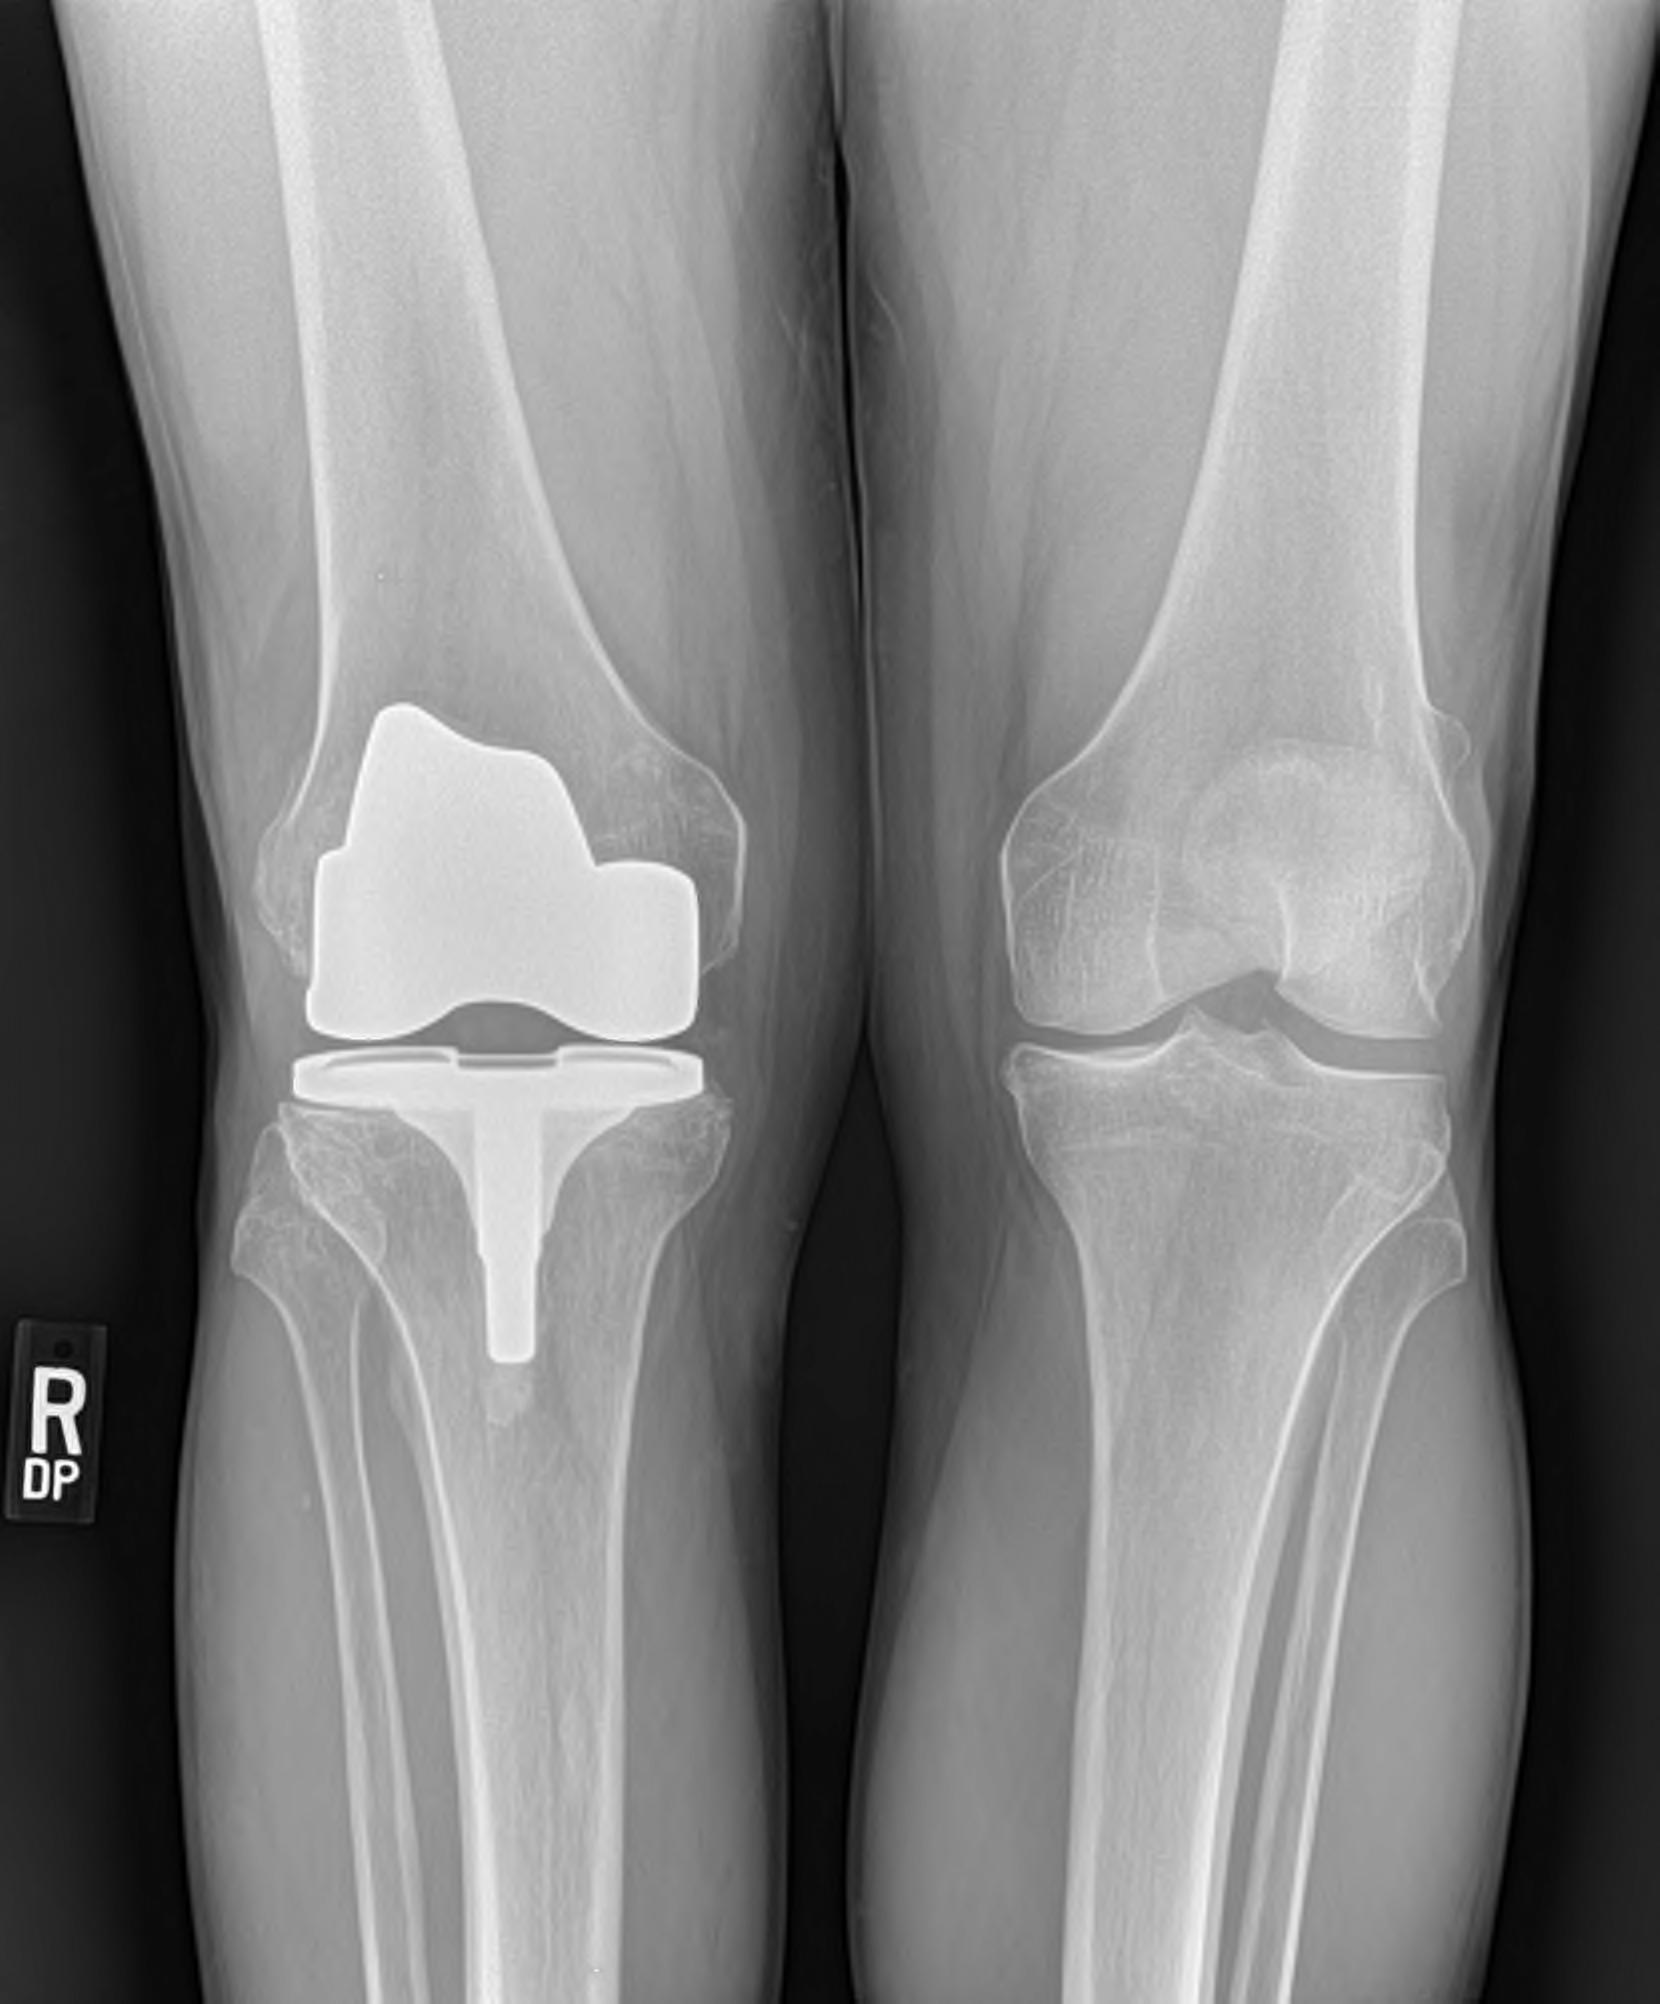

צילום זו בדיקה רפואית המיועדת ליצירת תמונה של איזורי גוף באמצעות מנה קטנה של קרינת רנטגן, ובכך עוזרת לרופאים לאבחן מחלה או פגיעה. צילומים הינם בדיקת הדימות הנפוצה ביותר. בעזרת קרינת הרנטגן ניתן ליצר תמונה סטאטית דו-מימדית של עצמות, הריאות, חלל הבטן ואיזורים אחרים בגוף.

בעזרת צילומי הרנטגן ניתן לאבחן מגוון מצבים רפואיים כגון שברים, דלקת מפרקים, דלקת ריאות, חסימות מעיים, וזיהוי אוויר חופשי ועצמים זרים (כגון מתכות) בגוף.